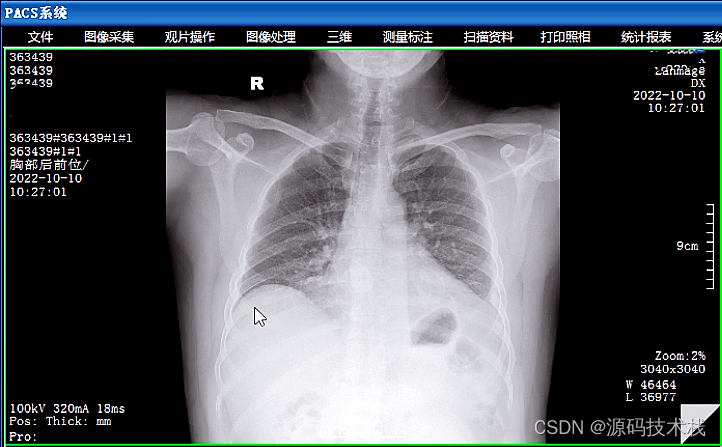

影像存储:PACS可以将医学影像数据以数字化的形式存储在服务器上,包括X射线、CT、MRI等各种影像类型。这些数据可以按照患者、日期、影像类型等进行分类和组织。

影像浏览和分析:PACS提供了影像浏览和分析的功能,医生可以在工作站上查看和分析影像,进行病情评估和诊断。同时,PACS还提供了一些辅助功能,如放大、缩小、旋转、对比度调整等,帮助医生更好地观察和分析影像。

1. 放射科:放射科主要进行普通X线片、电子计算机体层摄影(CT)、与磁共振成像(MRI)等医学影像工作,为临床医生提供诊断支持。

X光设备